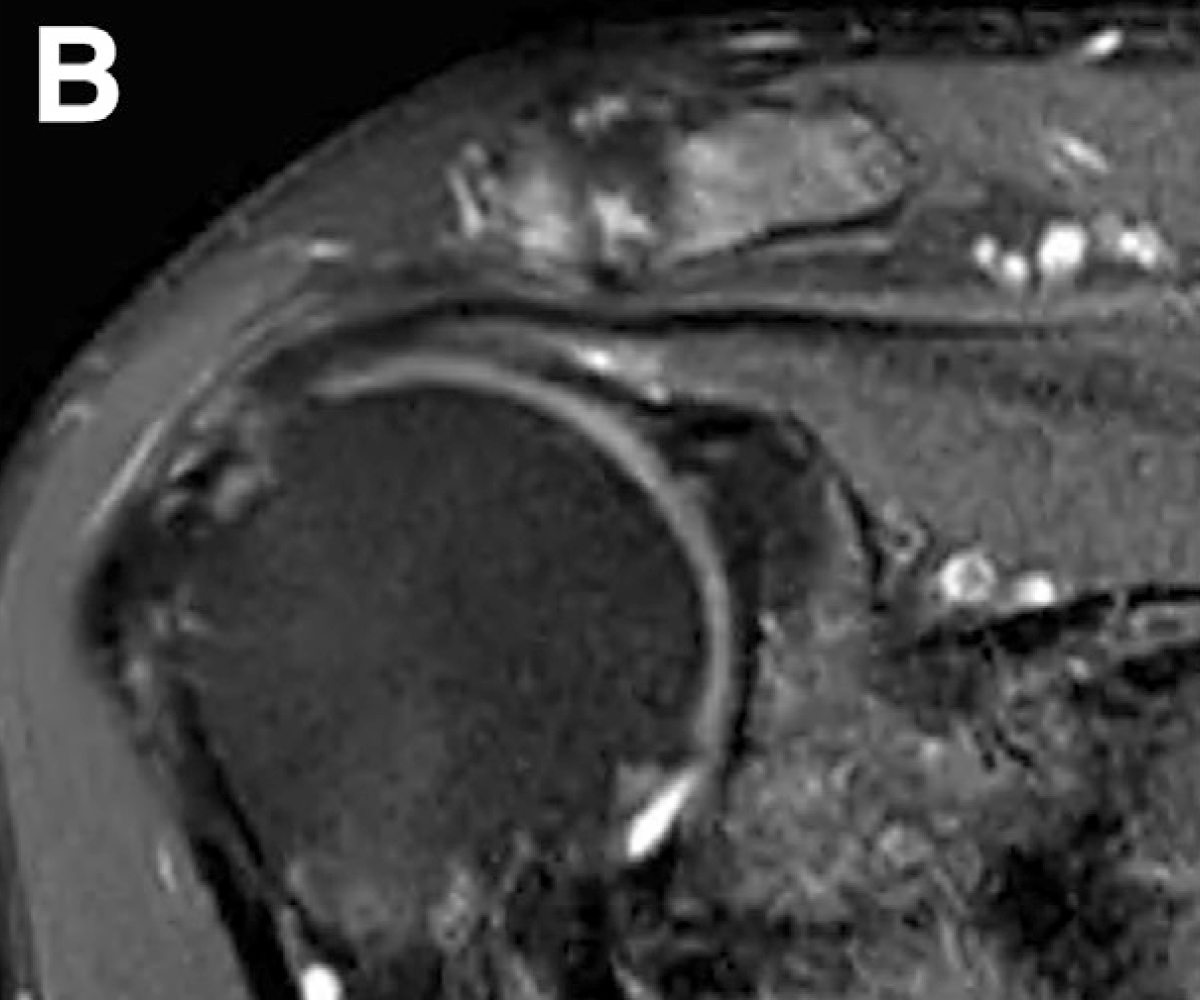

회전근개는 손상이 진행되면 부분파열이 되어 광범위 파열로 커질 수 있고,

옷감이 낡아 해지듯 힘줄도 점점 닳아 끊어지는 양상을 보입니다.

리제네텐은 파열된 회전근개 부위에 콜라겐 패치를 덧대어

새로운 힘줄 조직 성장을 지원하고,

약 6개월 이내 점진적으로 흡수되며 새로운 조직층으로 바뀌는 방식입니다.